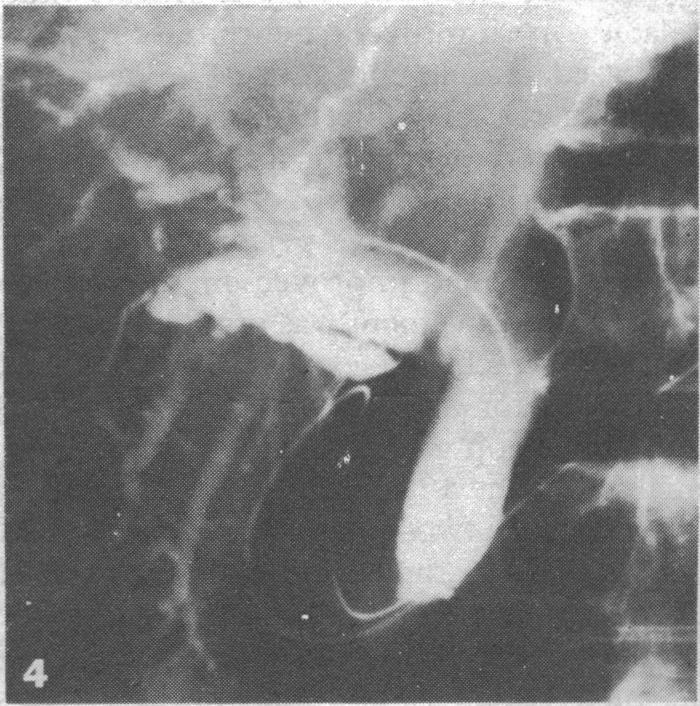

Interest is increasing in non-operative methods of relieving malignant obstruction of the bile duct, and drainage tubes and prostheses may be placed in the bile duct via the percutaneous transhepatic route. Two cases are described, however, in which a duodenoscope was used and the approach was via the papilla of Vater. This method allows temporary or permanent drainage tubes to be placed through malignant strictures. This endoscopic approach is less invasive and should be safer than that by the transhepatic route; furthermore, removing and replacing a blocked endoprosthesis should be easier. Further study is needed, as the procedure is technically more difficult and its role in managing biliary strictures has yet to be defined.

缓解恶性胆管梗阻的非手术方法越来越受到关注,引流管和假体可通过经皮肝穿刺途径放置在胆管中。然而,本文描述了两例使用十二指肠镜并经十二指肠乳头入路的病例。这种方法允许通过恶性狭窄放置临时或永久性引流管。这种内镜入路的侵入性较小,应该比经肝途径更安全;此外,取出和更换堵塞的内置假体应该更容易。由于该手术在技术上更困难,其在处理胆管狭窄中的作用尚未明确,因此需要进一步研究。